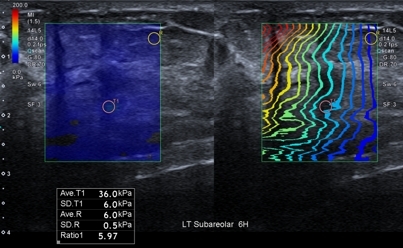

탄성초음파에서도 혹은 주변의 정상적인 조직과 비교하였을 때 뚜렷하게 단단한 성질을 보이고 있었고, 전반적으로 총조직검사를 통하여 확인이 필요하였습니다.